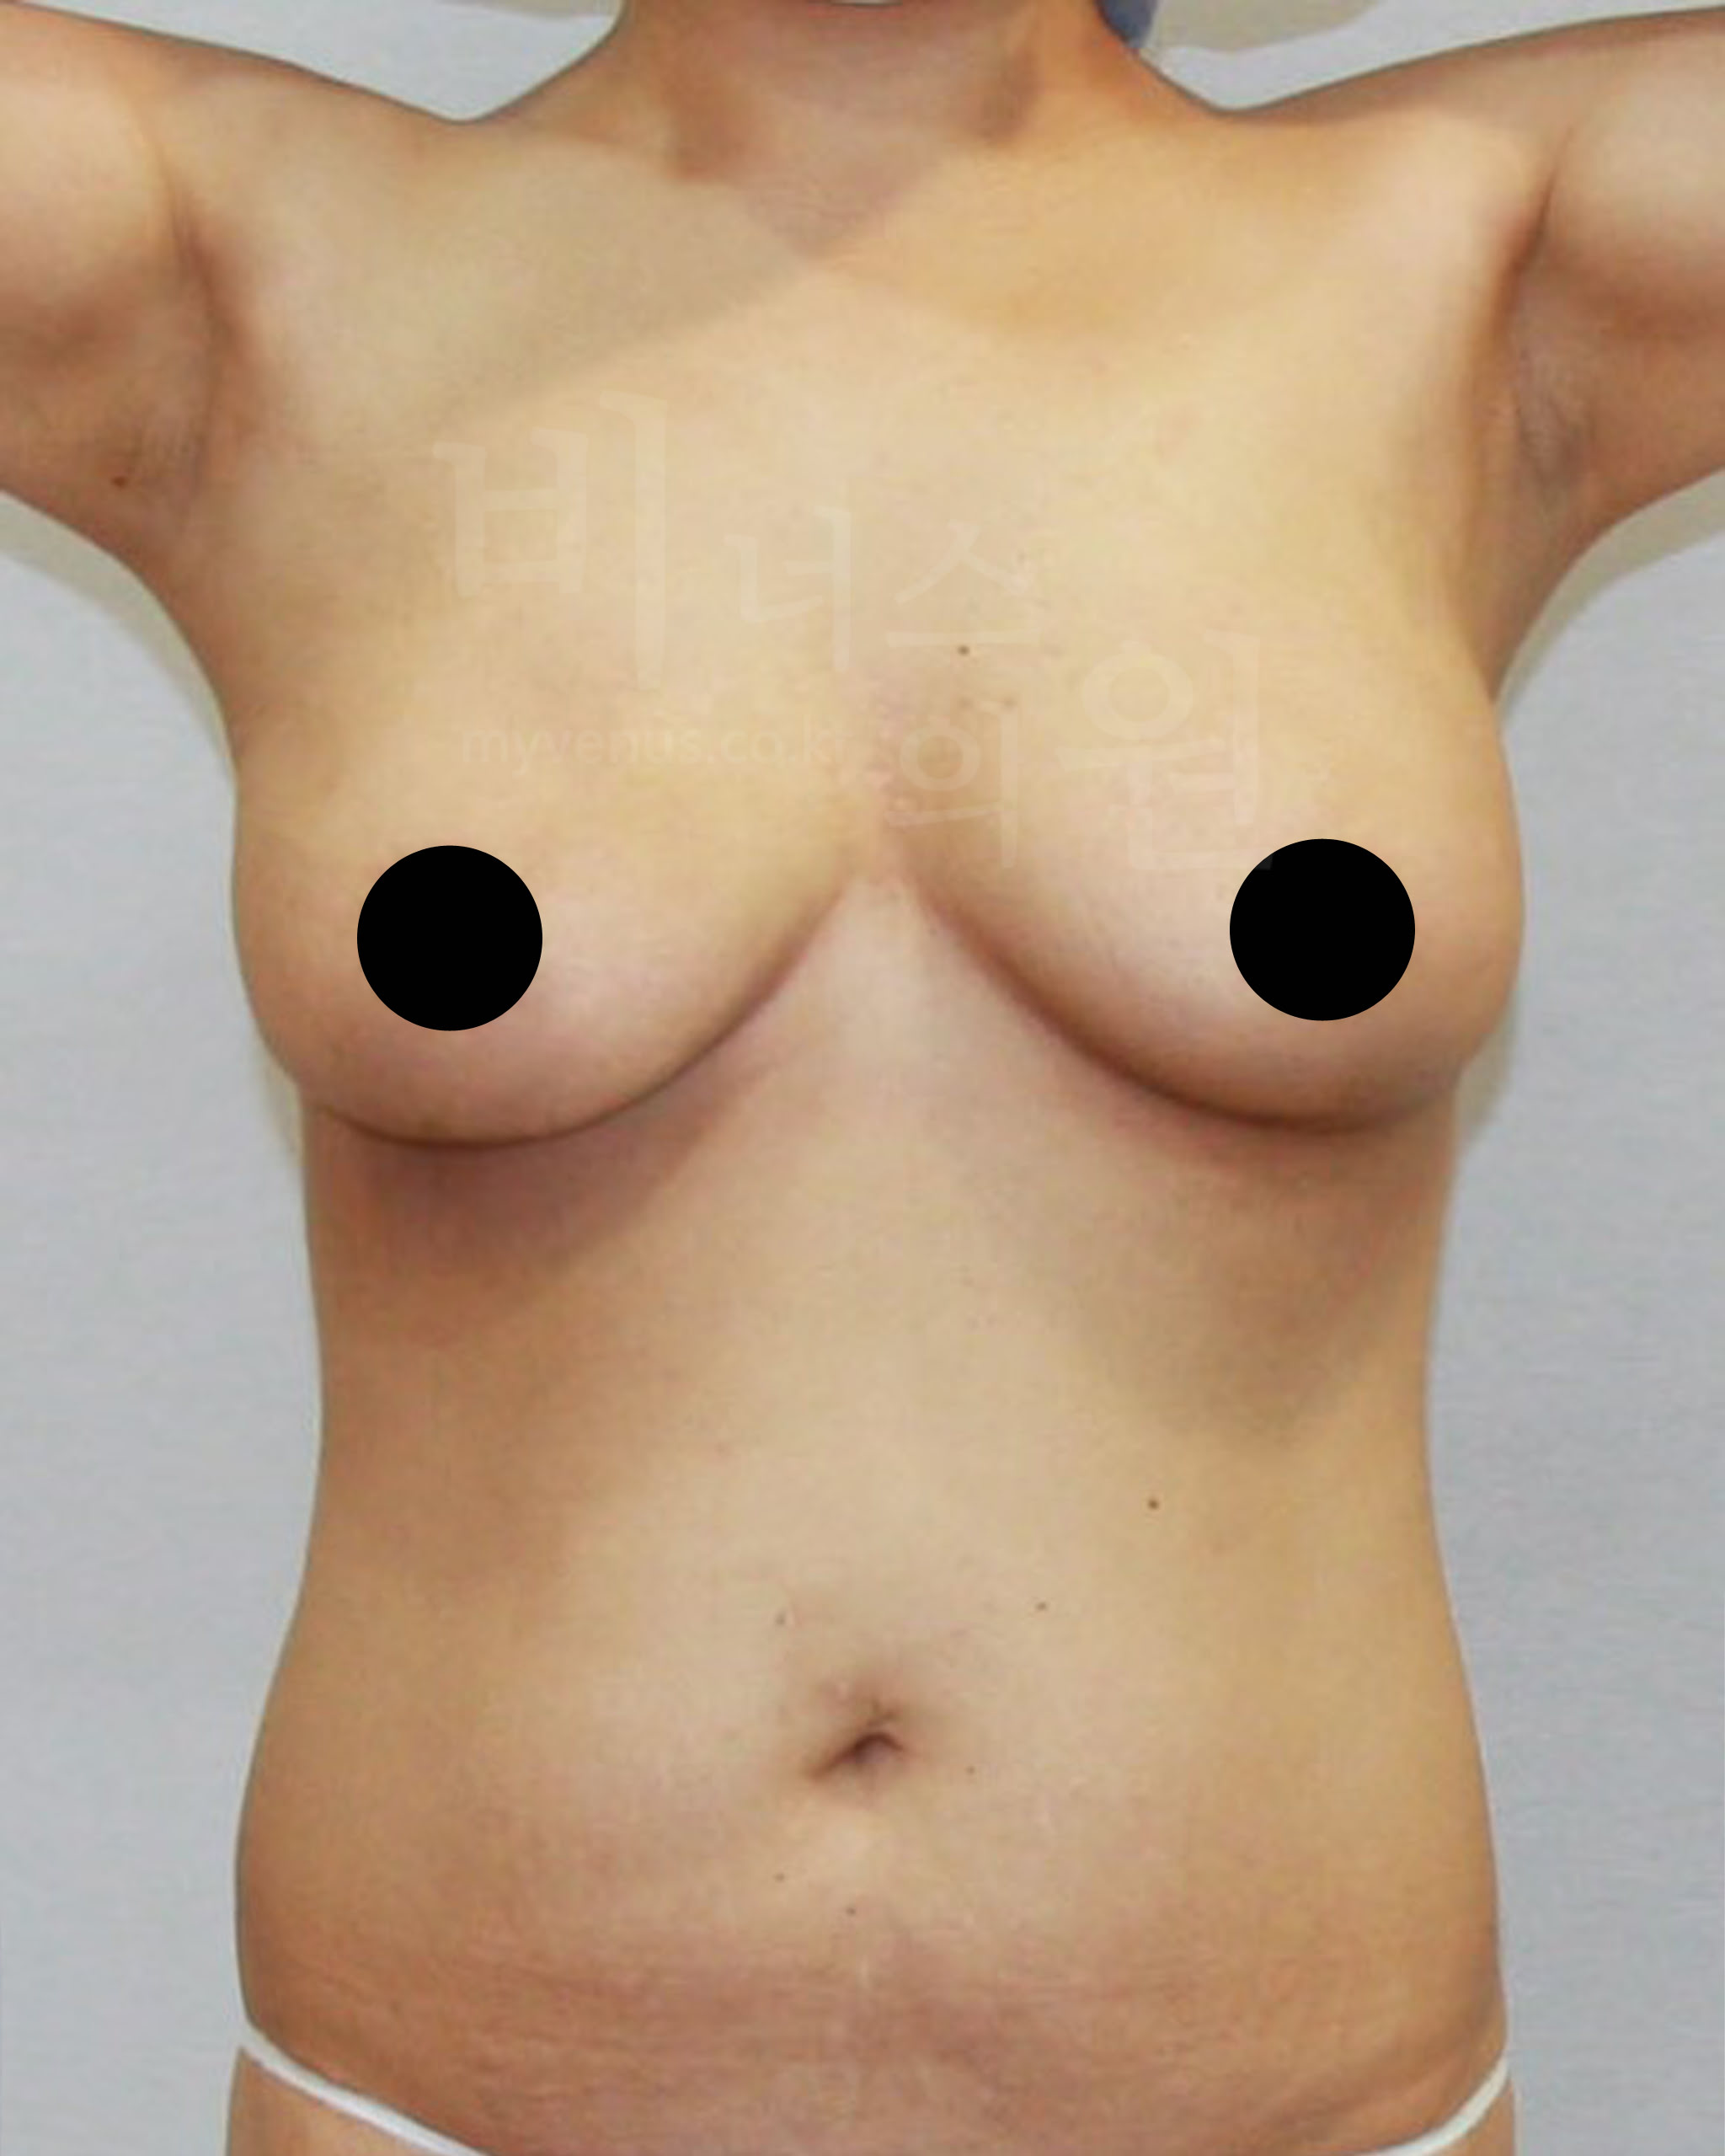

가슴축소 지방흡입 전 사진

처지고 무거워 밑으로 축 늘어져 있는 모습

가슴축소 지방흡입 후 사진

처지고 무거운 가슴이 교정된 모습

40대의 여성으로 사이즈 감소와 처짐의 교정을 위해 내원하셨어요. 탄력 있으면서 볼륨 있는 사이즈 감소를 원하셨어요. 가슴 축소, 부유방, 겨드랑이, 유방 옆구리 지방흡입으로 도움을 드리기로 했어요. 가슴 사이즈 감소로 무게감이 훨씬 줄어들어 보이며, 사이즈 감소와 탄력 있으면서 봉긋 업된 가슴이 되었어요.